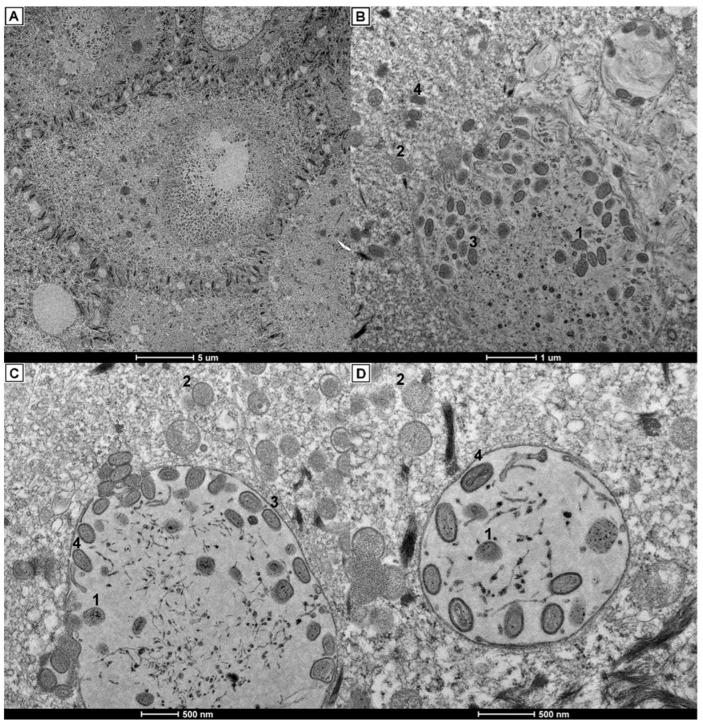

Avipoxvirus affects chickens and wild birds, and it is characterized by lesions on the nonfeathered parts of the body (the cutaneous form), or necrotic lesions in the upper respiratory tract (the diphtheritic form). In poultry farming, avian pox is usually controlled by live attenuated vaccines. However, there have been many reports of outbreaks, even in flocks of vaccinated birds. In the present study, different outbreaks of the emerging clade E avipoxvirus were detected in commercial breeder flocks of chickens vaccinated against fowlpox virus in Southeast Brazil. Clinical manifestations of these outbreaks included a marked prevalence of moderate to severe progressive lesions in the beaks of affected birds, especially in roosters with increased mortality (up to 8.48%). Also, a reduced hatchability (up to 20.77% fewer hatching eggs) was observed in these flocks. Analysis of clinical samples through light and transmission electron microscopy revealed the presence of Bollinger bodies and poxvirus particles in epithelial cells and affecting chondrocytes. PCR, sequencing, and phylogenetic analysis of major core protein () and DNA polymerase () genes identified this virus as clade E avipoxvirus. We also developed qPCR assays for open reading frames (ORFs) 49, 114, and 159 to detect and quantify this emergent virus. These results show the arrival and initial spread of this pathogen in the poultry industry, which was associated with harmful outbreaks and exacerbated clinical manifestations in vaccinated commercial breeder flocks. This study also highlights the relevance of permanent vigilance and the need to improve sanitary and vaccination programs.

禽痘病毒可感染鸡和野生鸟类,其特征为身体无羽毛部位出现病变(皮肤型),或上呼吸道出现坏死性病变(白喉型)。在禽类养殖中,通常通过使用弱毒活疫苗来防控禽痘。然而,已有许多暴发疫情的报道,甚至在接种疫苗的禽类群体中也是如此。在本研究中,在巴西东南部接种禽痘病毒疫苗的商业种鸡群中,检测到新兴 E 分支禽痘病毒的不同暴发。这些暴发的临床症状包括受感染鸟类的喙部出现明显的、中度至重度的进行性病变,尤其是死亡率增加的公鸡(高达 8.48%)。此外,这些鸡群的孵化率(孵化蛋数减少了高达 20.77%)也有所下降。通过光镜和透射电子显微镜对临床样本进行分析,发现上皮细胞和受影响的软骨细胞中存在 Bollinger 小体和痘病毒颗粒。通过对主要核心蛋白()和 DNA 聚合酶()基因的 PCR、测序和系统发育分析,鉴定该病毒为 E 分支禽痘病毒。我们还针对 ORF49、114 和 159 开发了 qPCR 检测方法,以检测和定量这种新出现的病毒。这些结果表明该病原体已在禽类产业中传播,并导致接种疫苗的商业种鸡群中出现有害暴发和恶化的临床症状。本研究还强调了持续监测的重要性和完善卫生及免疫接种计划的必要性。